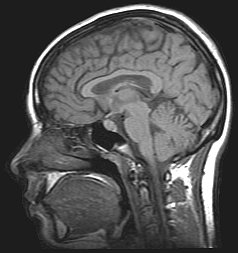

![]() Изображение головного мозга человека с внутричерепной гипертензией по результатам МРТ | |